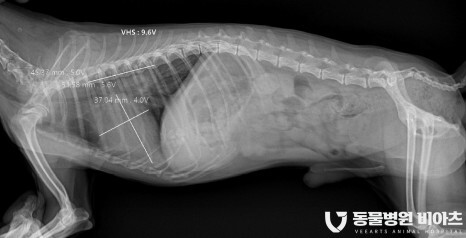

4. 엑스레이/초음파

엑스레이 (VHS, VLAS)

초음파(LA:Ao, LVIDDN)

방사선 촬영

방사선 촬영에서는

심장의 비대 정도

VHS(Vertebral heart size) 와

VL(Vertebral left atrial size)

를 측정합니다.